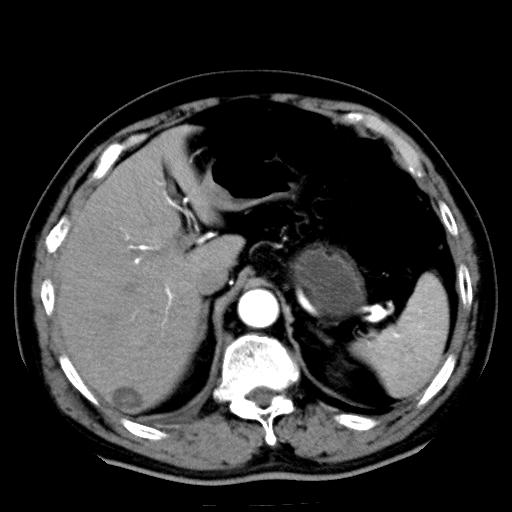

以下是引用zhctwbh在2008-8-23 14:20:00的发言:[br]囊肿合并出血

以下是引用zjb在2008-8-23 16:41:00的发言:[br]囊肿并出血可能性大。